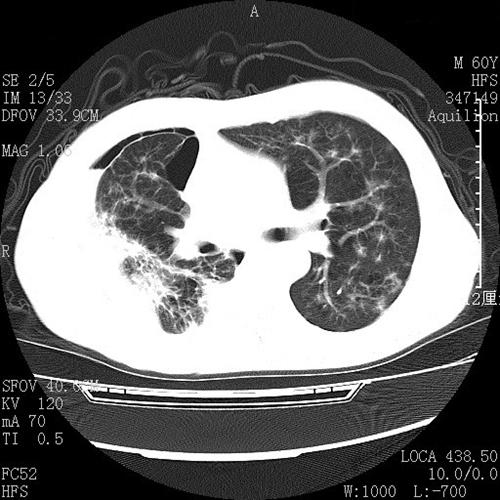

左肺腺癌術後胸腔內